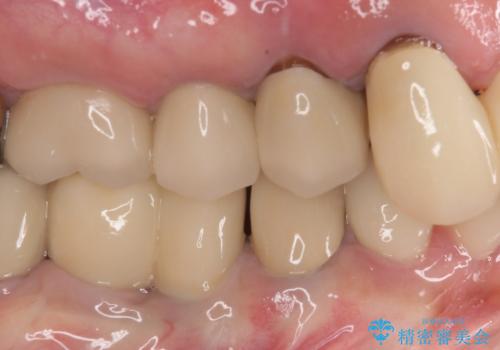

膿の出口が認められた頬側の歯槽骨は欠損が大きかったものの、インプラント埋入には十分な骨があり、無事に短期間で治療を終えることができました。